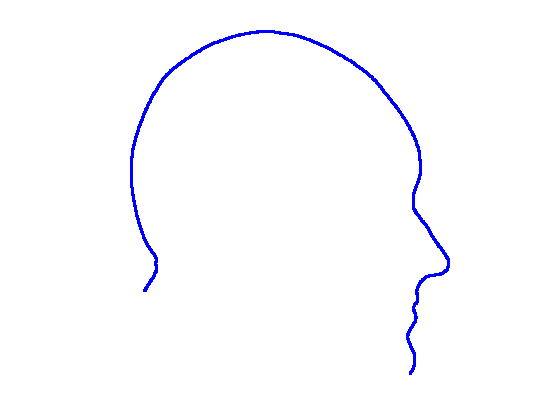

For each of the three segments, we determine the range of gradients on that segment by simple differencing between consecutive points. Each segment is rotated into a 2D frame such that maximum absolute values of positive and negative gradients are equal. Cubic spline contours are fitted to the three profiles and the head profile contour is reconstructed using the three individual cubic splines. Fig. 14 show examples of these.

|